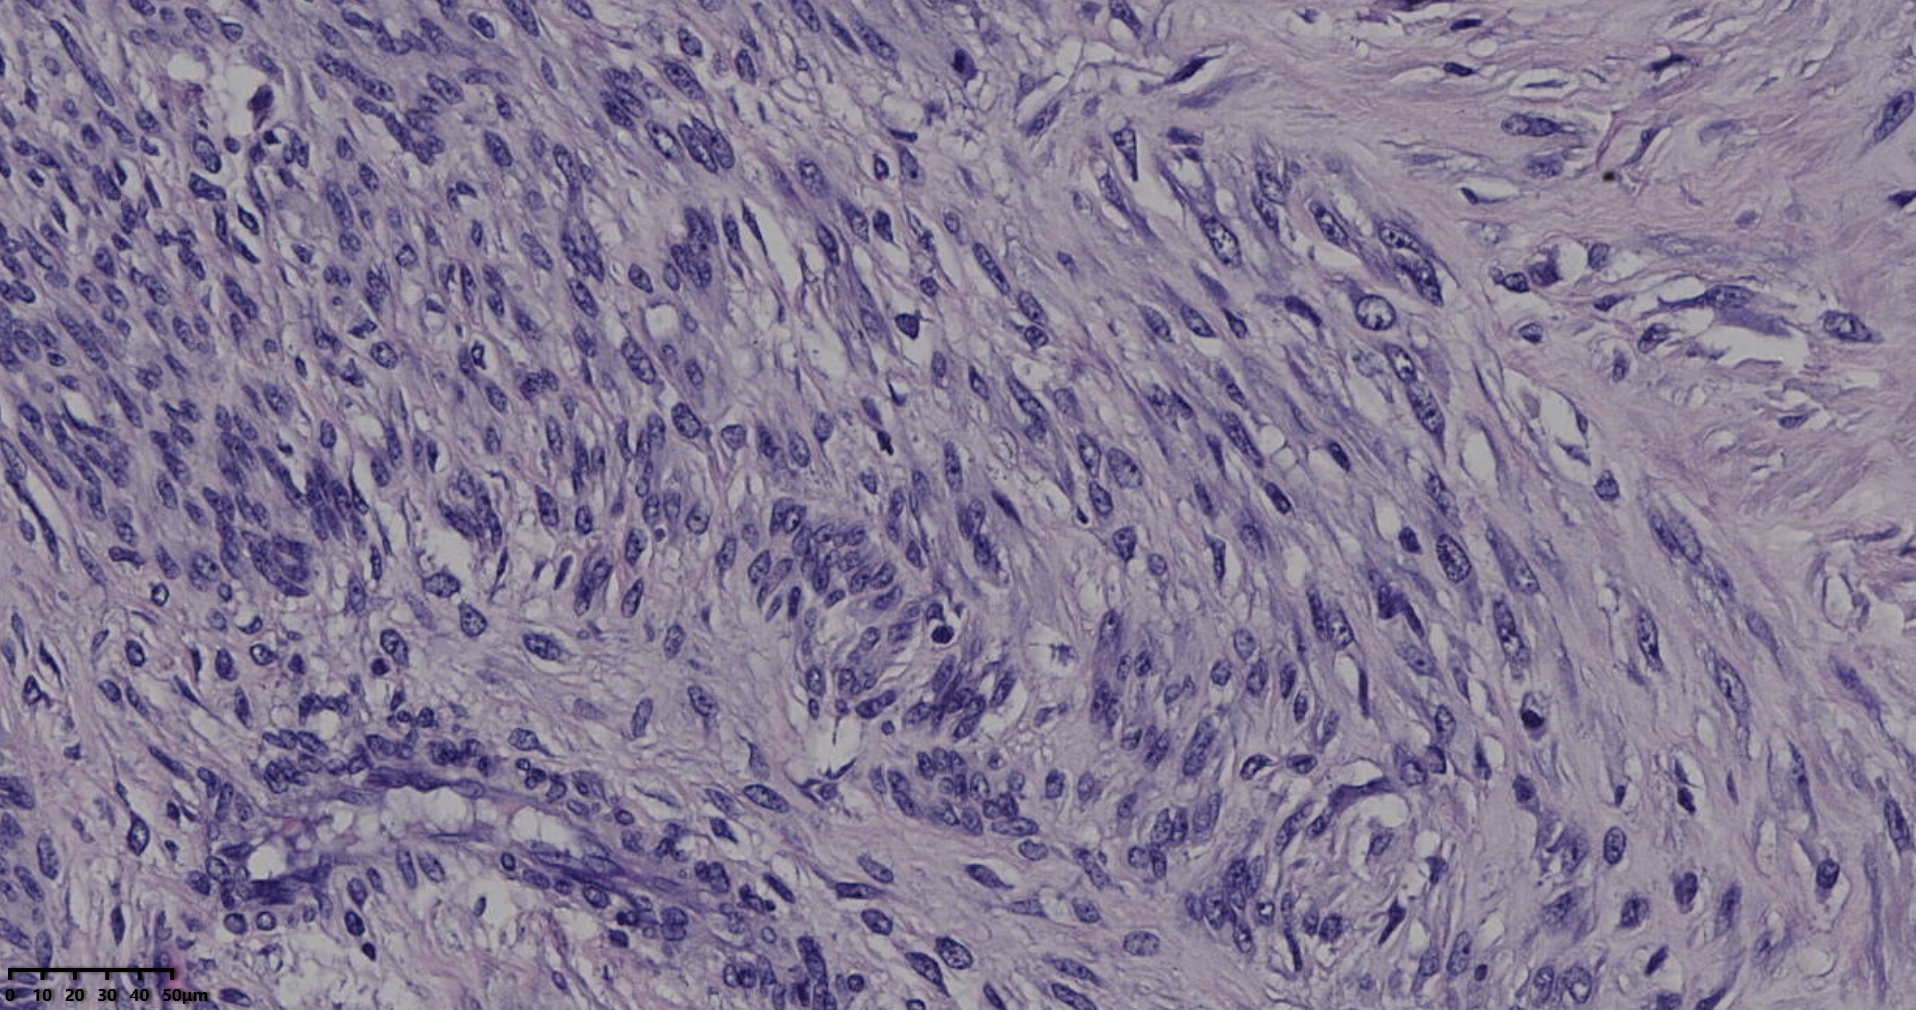

镜下所见小肿物无特殊,大肿物瘤细胞密集,中心区有变性、坏死,瘤细胞核有异型性。大肿物补充取材,发现,部分区域切面灰黄,这个区域,瘤细胞更密集,异型性更显著。肿物边缘有薄层正常平滑肌组织被覆,靠近边缘瘤细胞最密集,局部瘤组织内小血管较丰富。